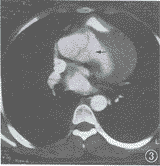

EBCT显示:主动脉升弓部显著扩张,升主动脉与左心室间可见一异常通道,直径约1.5 cm,长约3.0 cm。通道的主动脉端发自左冠状窦外上方,经肺动脉及右心室流出道后方进入左心室。通道和扩张的左冠状窦致右心室流出道受压变形。左心室增大,舒缩功能不良,射血分数为43%(图1~4)。诊断:先天性心血管畸形,主动脉-左心室通道。

图1 通道(↑)的主动脉侧开口位于冠状窦上方。升主动脉显著扩张

图2 通道(↑)内侧邻左冠状窦,外侧为升主动脉左侧壁及室间隔

图3 通道(↑)与扩张的左冠状窦压迫右心室流出道。前者的心室端开口于左心室